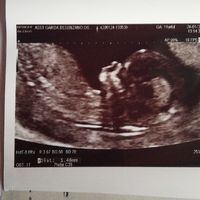

17+6 5 si inizia il 5 mese e.... femminuccia💕💕💕🌸

Cindy, Il 27 Febbraio 2020 alle 18:30

Eccomi ragazze per i miei soliti aggiornamenti oggi a 17+6 ho un accenno di pancia... La gravidanza prosegue benissimo. La mia bimba sta bene... Io ho smesso di vomitare il 17 febb a 17+3 e ho messo...